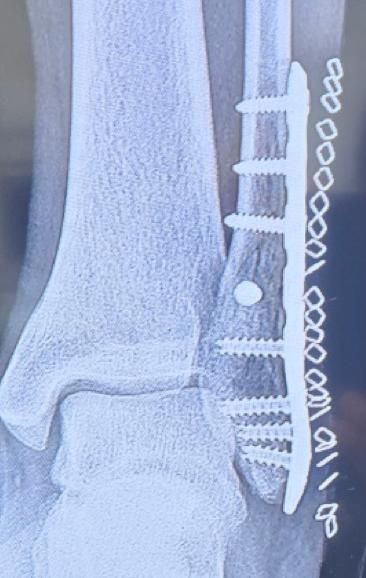

• 2번 째 사진

엑스레이 영상으로 추정컨데, 수상 당시 골절이 심각한 상태였을거라 예상됩니다.

그만큼의 골절이 생겼다면 신경 손상이 동반되었을 가능성이 높고, 이에 대한 회복에는 상당 시간이 소요됩니다.

깁스를 하다가 제거한지 얼마 안되었다면 아직은 회복하는 과정에서 나타나는 증상일거라 사료됩니다.

그러나 이는 골절과 수술 후 생길 수 있는 일반적인 상황에 대해 말씀드리는 바이며, 질문자께서 언급하신 중대 합병증의 가능성도 항상 고려해야 하므로 병원에서 정기적인 관찰과 치료가 유지되어야 합니다.